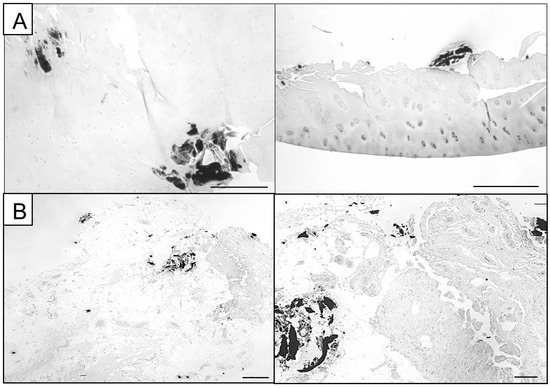

Figure 2.

Representative Von Kossa images of partly calcified joint tissue. (A) Calcifications can be embedded within cartilage tissue and located in the deeper layers exhibiting a powdery appearance (left panel) or presenting as calcified chunks located loosely at the chondrocyte surface (right panel, scale bars: 500 µm). (B) Synovial membrane specimens can exhibit both smaller calcifications and bigger calcified chunks that are integrated into the surrounding tissue or loosely presented aside (scale bars: 500 µm).

Von Kossa utilizes a two-step chemical reaction between silver ions and calcium phosphates, leaving a transient yellow colour. Under UV light exposure, organic matter reduces the bound silver ions to metallic silver, resulting in the characteristic black colour. Only the initial yellow colouration after the first reaction directly labels calcium phosphate while the later black colouration is a secondary result caused by organic material [39].

Further, multiple studies demonstrated discrepancies between Von Kossa-stained calcification nodules and spectroscopic detection of calcium phosphates, rendering Von Kossa staining alone insufficient for the identification and quantification of calcifications [25,40]. Therefore, high-resolution imaging techniques should be used to verify/identify the presence and nature of calcified deposits and improve their qualitative analysis. Here, we utilized Alizarin Red S (Figure 1) and Von Kossa images (Figure 2) to select ROIs for further microscopic and spectroscopic analysis.